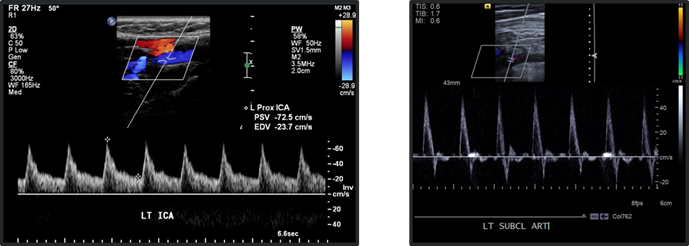

both of these are normal waveforms. Which is an upper and which is a lower extremity vein?